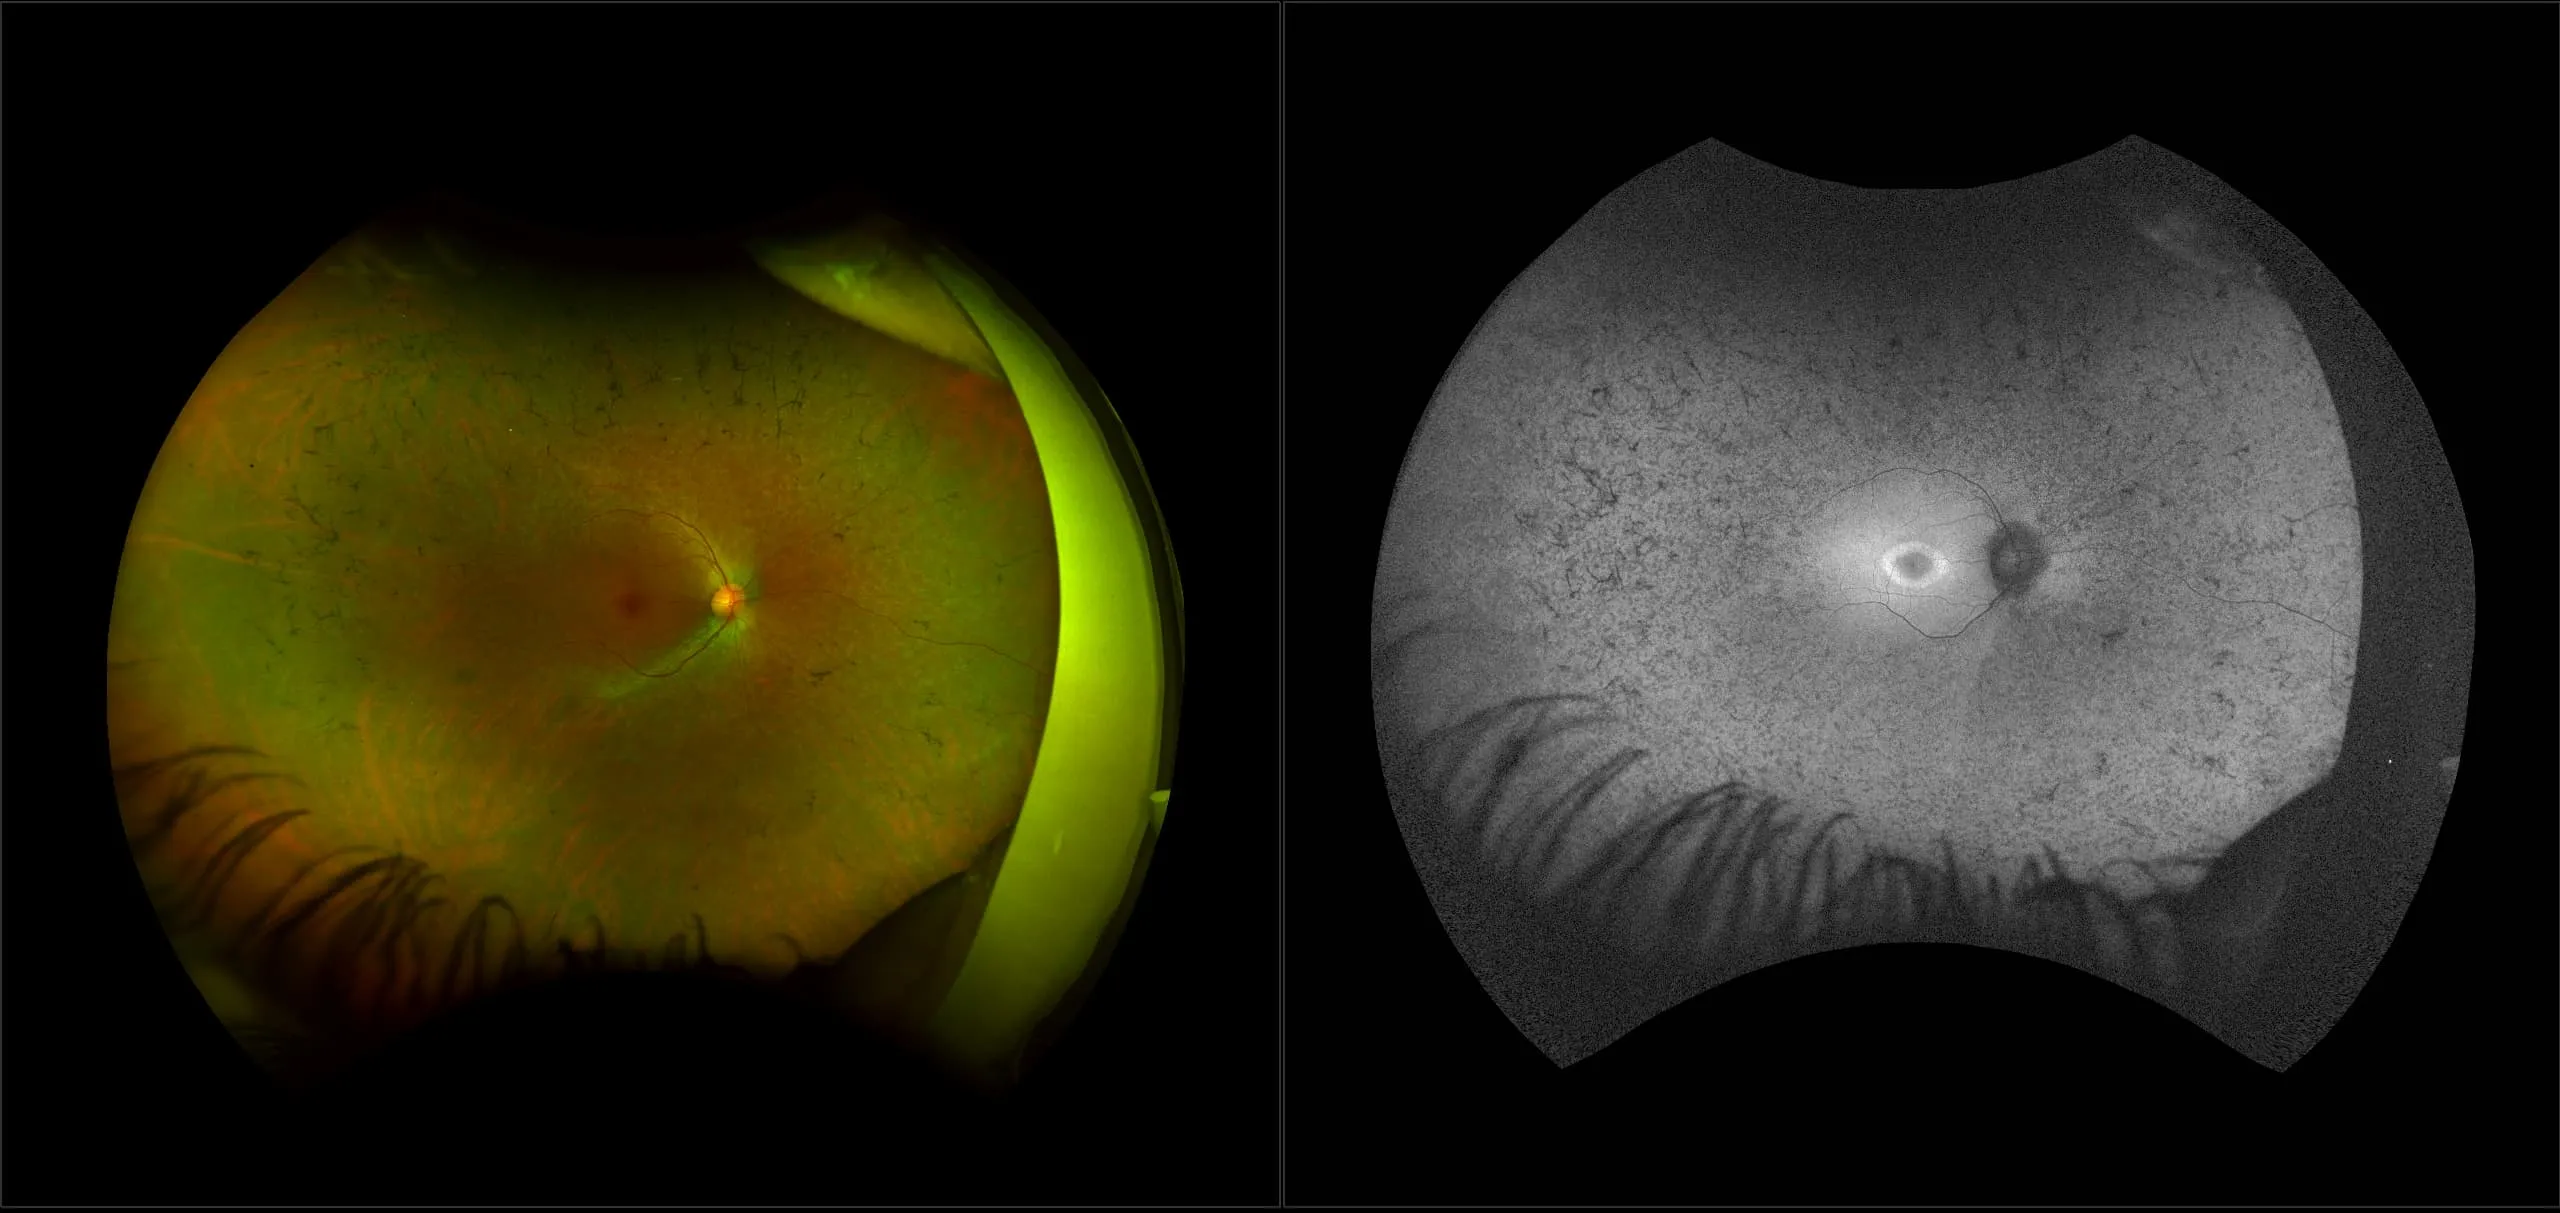

optomap® Recognizing Pathology

This material is designed as a searchable reference resource to support clinical decision-making. The information contained here should be used as general guidance when viewing optomap and OCT images from Optos devices. The differential diagnosis should be made under the direction of the responsible physician. These images were taken on the latest ultra-widefield optomap devices.

The Cases and Images

optomap Recognizing Pathology is searchable by pathology and/or optomap image modality. You may search by multiples of each selection. Each individual case is represented by the accompanying thumbnail image. Most cases include several different optomap image modalities. To view a full description of the case, please click on the thumbnail. Each image in the case will be made available through our OptosAdvance software which provides multi-dimensional visualization of digital images to aid in the analysis of anatomy and pathology. Support and pathology definitions can be found by selecting one of the buttons, above. Should you have questions, please complete the form below.